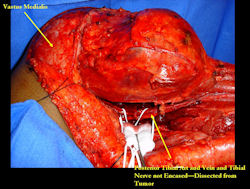

Examples of radical limb sparing surgeries for osteosarcomas in various anatomic locations (distal femur, proximal tibia, proximal humerus, scapula)

In each case, the tumor and bone from which it arose were resected. This required meticulous dissection, mobilization and preservation of adjacent pertinent neurovascular structures. In each case presented here, the defect was reconstructed with a special modular segmental tumor prosthesis. This also replaces the adjacent joint in many instances.

Limb-sparing surgery for osteosarcoma of distal femur – Intraoperative photos